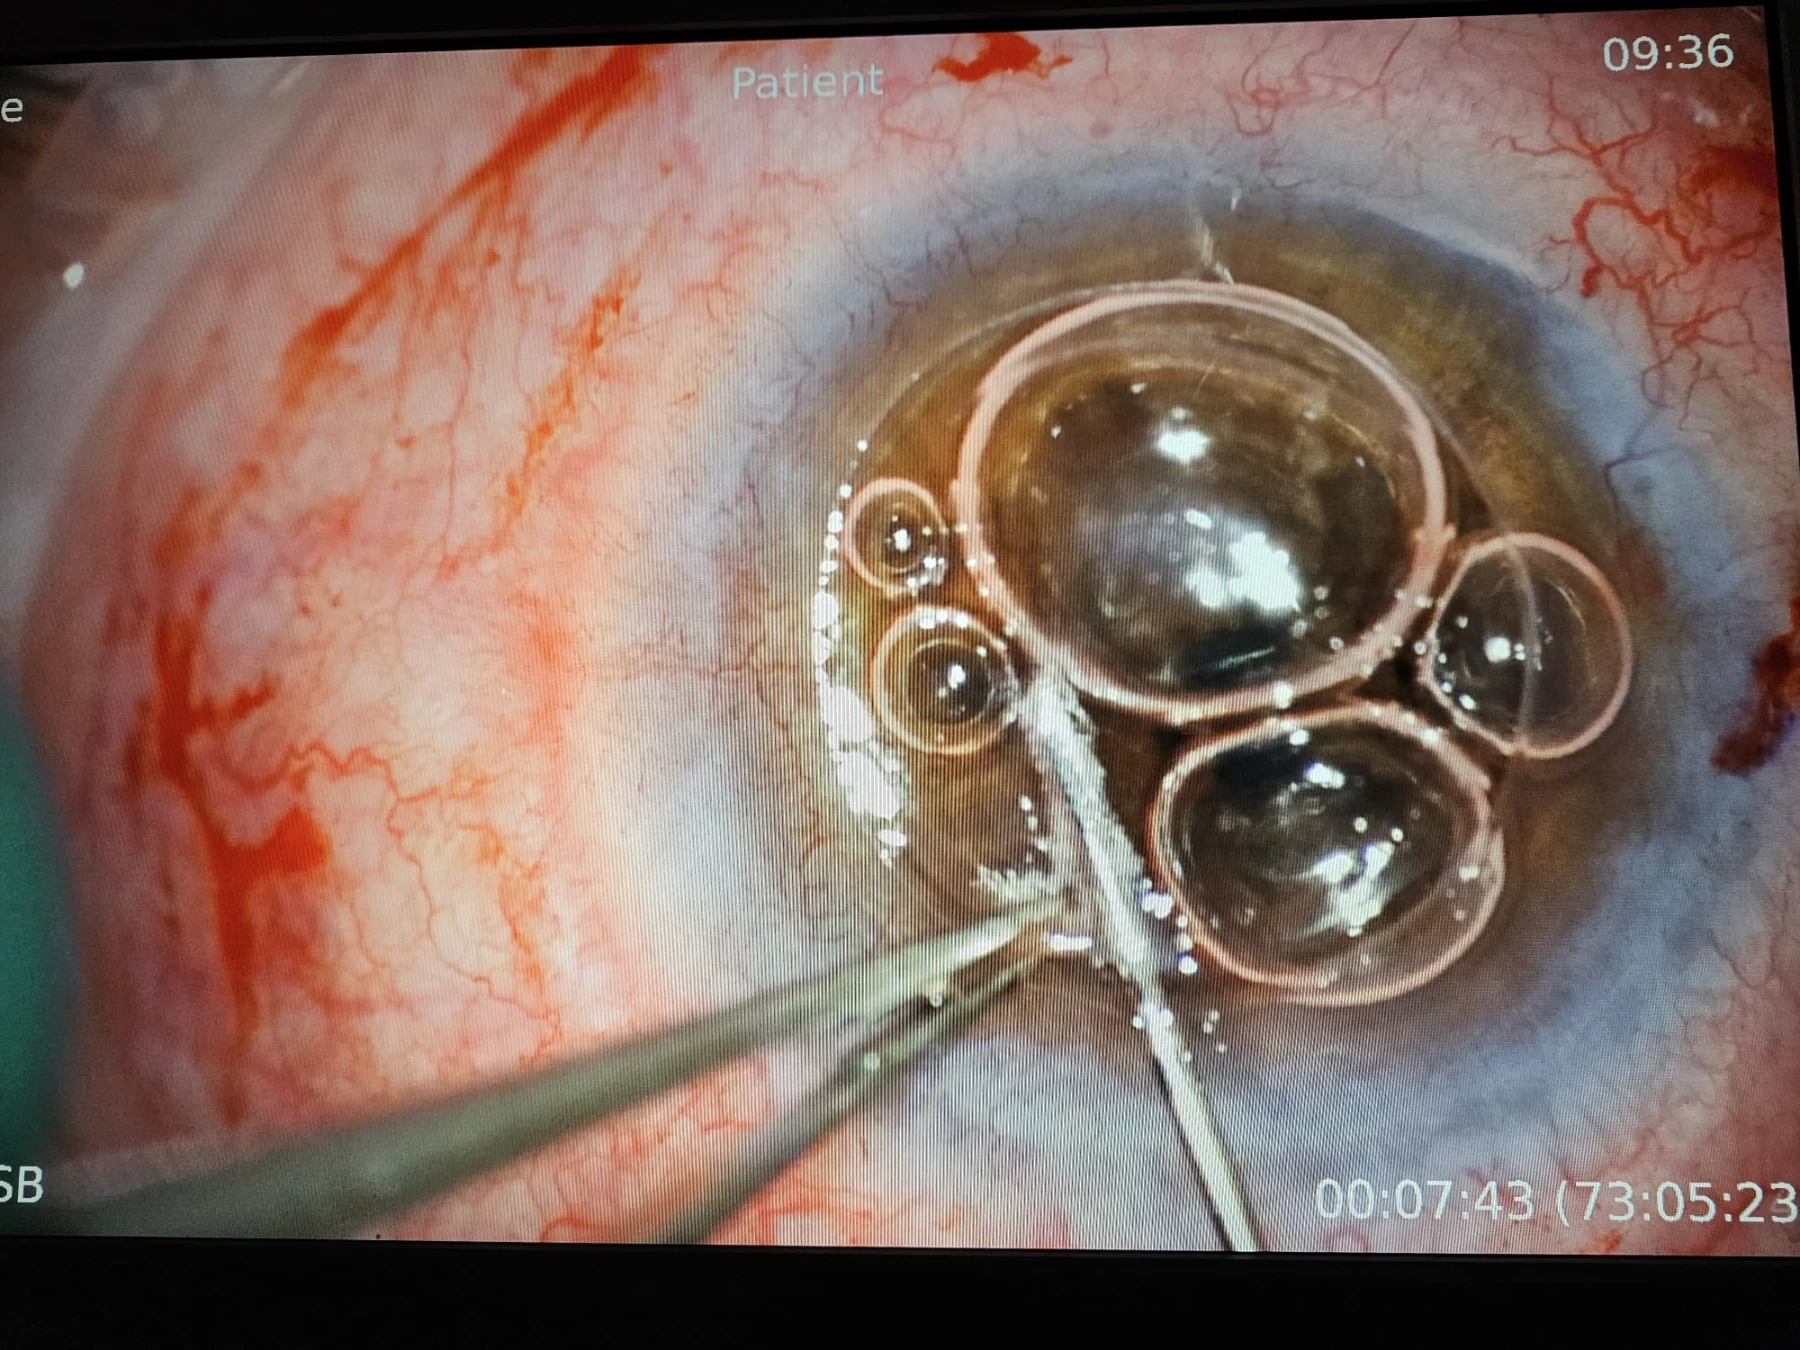

Keratoconusul este una dintre cele mai frecvent întâlnite distrofii corneene, constând în deformarea neregulată și progresivă a corneei, care ia o formă de con, cu subțiere extremă în vîrful lui, pînă la complicația de “spargere” a acestei zone foarte subțiate, urmată de hidrops cu perforație sau / și de cicatrici fibroase în vârful acestui con. În stadiile lui cele mai avansate, când vederea pacientului este foarte scăzută, singurul tratament este operația de transplant de cornee, iar tehnica de elecție este transplantul lamelar anterior DALK, deoarece, prin acesta, se păstrează endoteliul cornean propriu al pacientului, endoteliul fiind stratul cel mai “valoros” al corneei, dar și cel răspunzător pentru 90% din situațiile de respingere a grefonului – de aceea, dacă se poate păstra, merită păstrat!

Iar când pacientul este foarte tânăr (17 ani în cazul de azi) și boala e avansată la ambii ochi, tânărul neputând să se descurce singur, nu doar că operația se impune cât mai repede, dar e de dorit să fie un transplant lamelar anterior DALK sau unul perforant “Mushroom”, cu păstrarea unei suprafețe cât mai mari din endoteliul propriu pacientului.

Tehnologia femtolaser este de mare folos în ambele tehnici menționate. Mai jos, cîteva secvențe din operația efectuată de dr. Cristian Moraru.